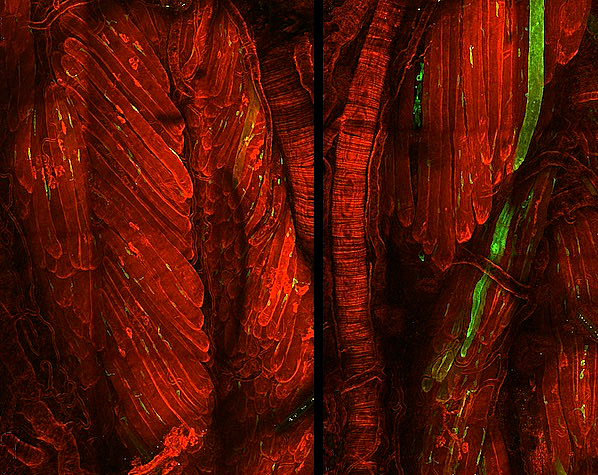

Les característiques que definixen les cèl·lules mare són la seua capacitat de convertir-se en diversos tipus cel·lulars i la seua habilitat per a autorenovar-se. Aquesta capacitat d’autorenovació garantix el manteniment de les reserves de cèl·lules mare en el cos i, si els científics saben aprofitar-la bé, també al laboratori. Quan es mantenen cultius de cèl·lules mare al laboratori, els investigadors solen utilitzar diferents combinacions de factors específics per a cada tipus de cèl·lula mare. No obstant això, investigacions recents han identificat un punt de control comú (la quinasa reguladora GSK3), que, quan s’inhibix, manté la capacitat d’autorenovació en diversos tipus de cèl·lules mare i en diferents espècies. De fet, la inhibició de GSK3 ha permés cultivar conjuntament epiblasts de ratolí i cèl·lules mare embrionàries, com es mostra a la imatge (en verd i roig), mantenint alhora les seues identitats pròpies, cosa que fins ara era impossible. A més de millorar les tècniques de cultiu de cèl·lules mare, el descobriment d’aquest punt de control comú podria tindre aplicacions clíniques per a millorar la salut i la regeneració de teixits envellits.

Imatge de Duo Wang/Ying Lab/USC Stem Cell. Publicació de Duo Wang i Xiukun Wang, i col·laboradors/es

Eli and Edythe Broad Center for Regenerative Medicine and Stem Cell Research at USC, Keck School of Medicine, USC, Los Angeles, CA; Epigenetics and RNA Biology Laboratory, National Institute of Environmental Health Sciences, Durham, NC, EUA

Publicat en Cell Research, abril de 2026